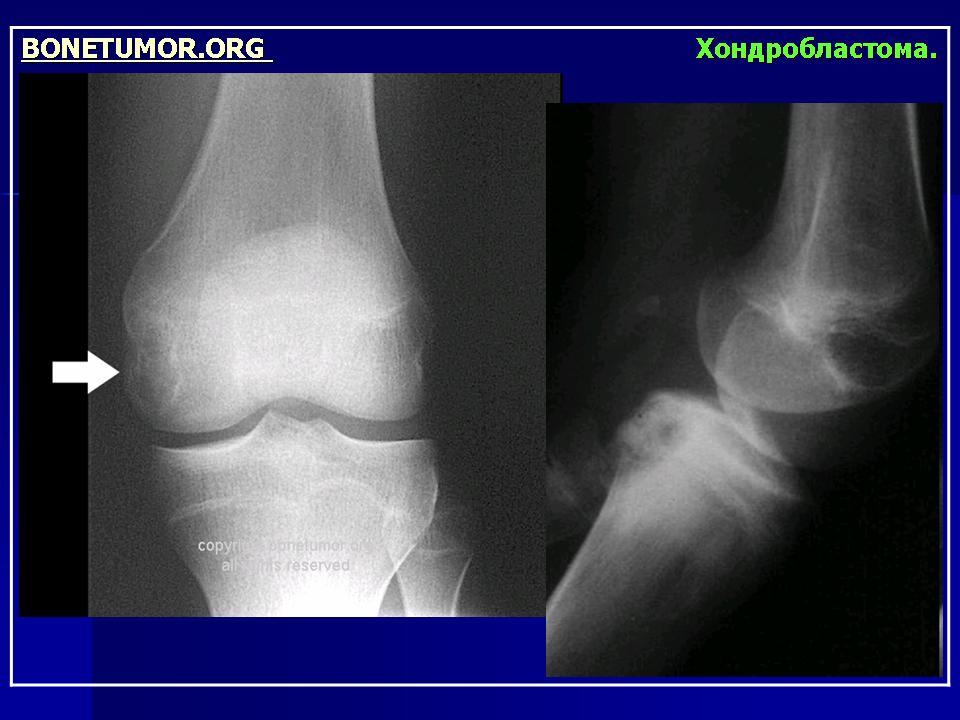

Рентгенологически хондробластома представляет собой сравнительно большой (2-4 см) очаг округлой формы, четко отграниченный от окружающей кости склеротической каймой. На фоне очага в большинстве случаев, но не обязательно определяются плотные включения, напоминающие хлопья ваты.

Рентгенологическая картина. Хондробластома выглядит как небольшой, от 3 до 6 см литический очаг, центрально или эксцентрично расположенный, с четкими контурами, занимающий около половины площади эпифизарной зоны. Хондробластома плоских костей и мелких трубчатых костей больших размеров, может сопровождаться припухлостью мягких тканей, вздутием кости и периостальной реакцией. Распространение процесса на метафизарную зону встречается часто.